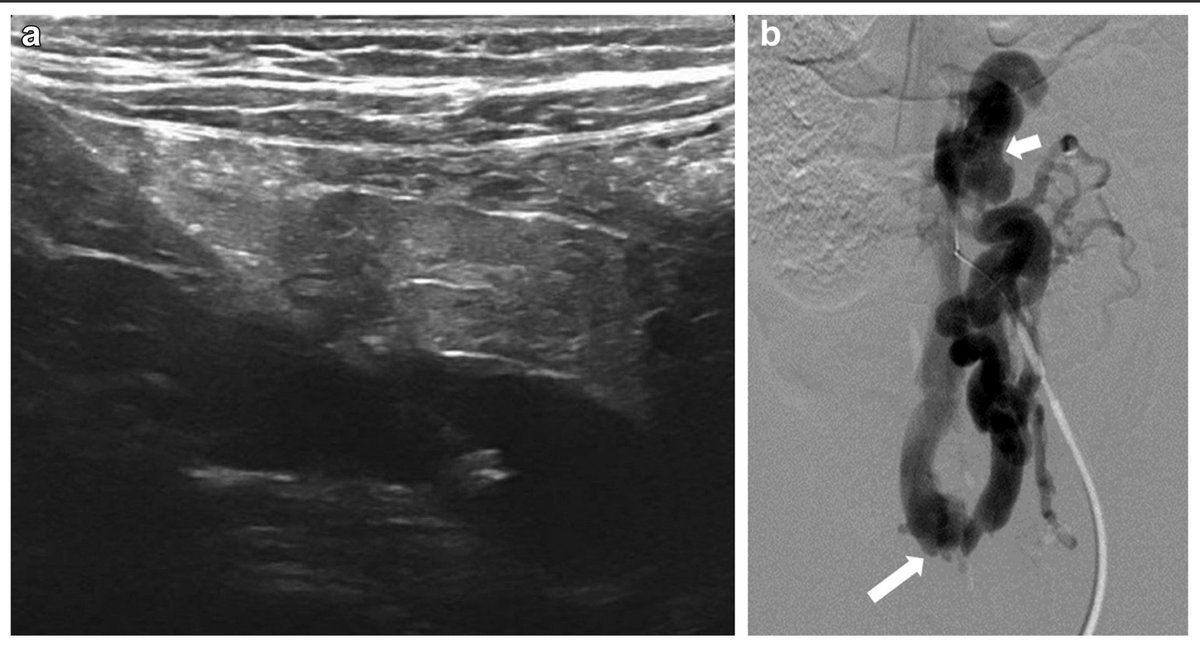

Better visualization, smarter planning. In this JVS-VL pilot study, CEUS + UHFUS showed promise for improving preop mapping and streamlining LVA in patients with lymphedema.